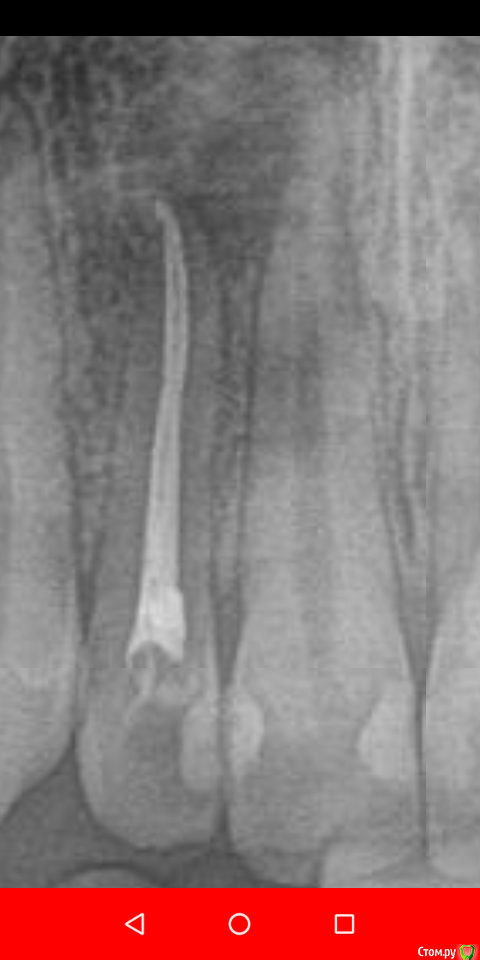

Daria_357 Опубликовано 21 августа, 2020 Поделиться Опубликовано 21 августа, 2020 Здравствуйте, резко появилась сильная неутихающая боль в 12м зубе, на третий день мне смогли оказать скорую помощь, поставив лекарство(убивающее нерв). Утром боль прошла, но опухло сильно лицо - вскрыли десну, поставив дренаж. Позже канал долго чистили и оставили временную пломбу на две недели. 18.08 приняли решение ставить постоянную пломбу. Первая пломбировка была неудачная-на снимке пломба не доходила до верхушки примерно на миллиметр. Вторая попытка закончилась так же, врач сомневалась, советовалась с коллегой, но оставила как было. На прицельном снимке видно, что не доходит в области "поворота" канала около 1мм, но у меня есть только ортопантомограмма, на ней видно только небольшую темную точку, и есть вид формы канала до пломбировки(прикрепила). По мнению врача, дойти дальше не получается так как канал изогнут. На мой вопрос почему тогда с временной пломбой пломбировка была идеальной(там пломба шла выше чем сейчас и истончалась к кончику), - врач сказала, что тогда канал был более узким, а сейчас она его расширила(?). Так же врач высказывала мнение, что если канал не запломб.до конца, то ничего страшного, - сделаем резекцию. Скажите, пожалуйста, стоит ли мне наставивать на перепломбировке уже сейчас, а не дожидаясь воспаления?Этот зуб отмечен синим. И второй вопрос по поводу плана лечения. Мне хотят с соседним передним зубом то же самое делать уже сейчас, так как есть опасения, что воспаление приблизится к нему. Верно ли это? Этот зуб отмечен красным. В этой же клинике мне года три назад вывели промбировочный материл за канал, достаточно много, но вариант, что воспаление из-за этого не подтвердили.Этот зуб отмечен зелёным. 2 Ссылка на комментарий